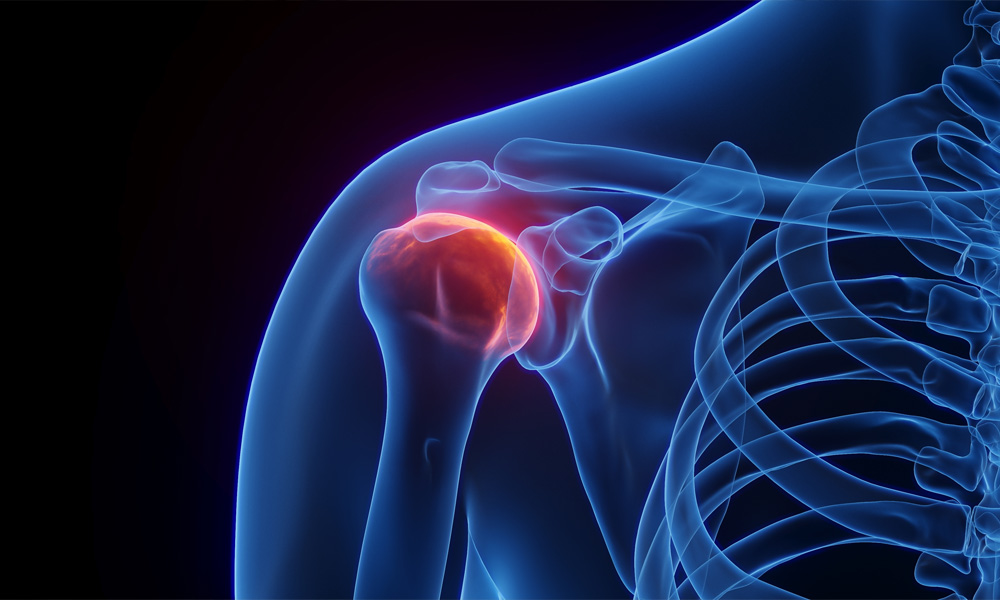

Comparación de la inyección intraarticular de ozono médico y esteroides en pacientes con capsulitis adhesiva Resumen Objetivo La capsulitis adhesiva es una enfermedad que se caracteriza por una disminución significativa del rango de movimiento (ROM) activo y pasivo de la articulación glenohumeral, acompañada de dolor. La ozonoterapia ha demostrado resultados prometedores en el tratamiento de […]